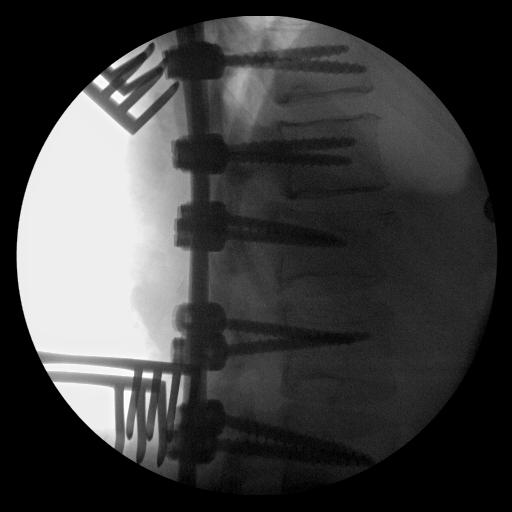

Posterior instrumentation

Indication

- < 7 gaines criteria

- no neurology

Technique

- ligamentotaxis clears canal / PLL acts as bowstring

- pedicle screws lumbar, avoided in thoracic

- use transverse process and pedicle hooks in thoracic

- bone graft inserted via pedicles

- need to do before 5 days post injury